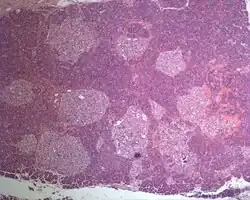

| Photographic image of the numerous islets of various sizes in the pancreas of a patient with Mahvash disease | |

Most patients with Mahvash disease are diagnosed in adulthood. Patients with Mahvash disease usually present with vague abdominal discomfort. Imaging with CT or MRI identifies a very large pancreas with one or more tumors. Biochemical testing shows marked hyperglucagonemia (hundreds-fold elevated). If the tumors are resected, they are found to be neuroendocrine tumors that usually express glucagon. In the tumor margin, pancreatic alpha cell hyperplasia is pervasive, numerous large islets composed of mostly alpha cells are evident, and multiple microadenomas and small neuroendocrine tumors often are present. The pancreatic neuroendocrine tumors are the main health concern for patients with Mahvash disease. Although the tumors commonly are indolent, death due to liver metastasis has been reported.[3] In patients with complete loss of glucagon receptor function, Mahvash disease can present at younger age with portal hypertension and hepatic encephalopathy.[11]